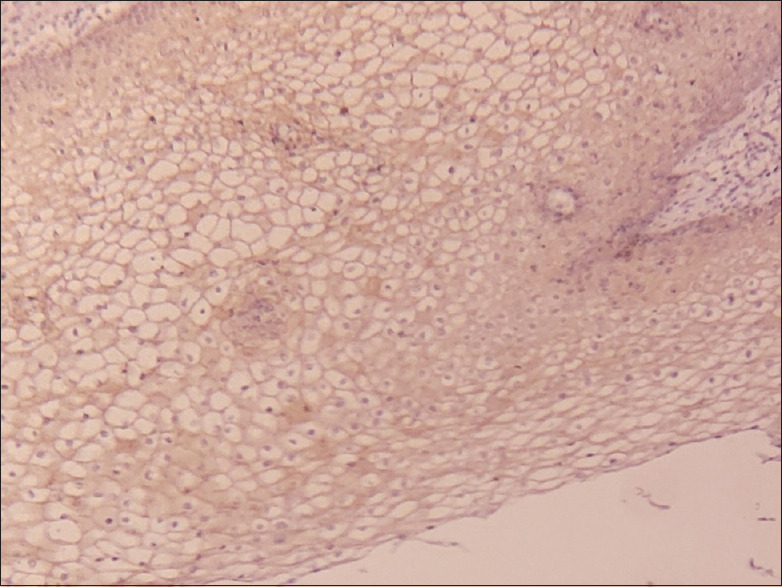

Materials and methods: A total of 50 archival lymph node blocks, both positive and negative neck nodes of the patients treated for OSCC, were used for the assessment of DSG1 and 3 expressions by immunohistochemistry (IHC) following their histopathological examination. The assessment of IHC staining was conducted by two independent maxillofacial pathologists as per the grading criteria in all the lymph node sections.

Results: A total number of 88 nodes were assessed, of which 27 were positive on histopathological assessment. DSG1 and DSG3 positivity were noted and varied between 11.4-12.5% and between 20.5-22.7% of positive nodes, respectively, between the observers. Cronbach's alpha was calculated for interobserver reliability for positive identification of metastatic lymph nodes. Area under curve (AUC) values for DSG1 were 0.478 and 0.02 for DSG3, and not so statistically significant value for DSG1 was obtained (P > 0.05) compared to DSG3 (P = 0.000).